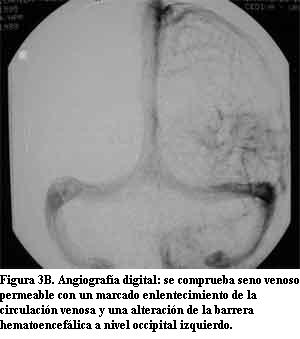

Niña de 10 años, sin antecedentes pre ni perinatales que a los 10 meses de edad, luego de un traumatismo de cráneo de intensidad leve, presentó crisis caracterizadas por vómitos, desviación óculo-cefálica a izquierda e hipotonía global, con sopor posterior, que se reiteraron en el curso de 24 horas. Su examen físico fue normal. En esa oportunidad se le realizó fondo de ojo, tomografía de cráneo (TC) (figura 1A) y electroencefalograma (EEG), que fueron normales. Evolucionó favorablemente hasta la edad de 4 años, cuando presentó nuevamente crisis epilépticas parciales complejas, con un episodio de status epilepticus. El EEG mostró signos de sufrimiento cerebral focal a nivel parieto-occipital izquierdo. En la TC se observó una imagen hiperdensa occipital izquierda (figura 1B). La resonancia magnética (RM) mostró un área de realce leptomeníngeo con el gadolinium en la misma topografía en relación con una corteza cerebral de aspecto atrófico, así como el plexo coroideo ipsilateral aumentado de tamaño (figura 2). En la angiorresonancia se observó una disminución de la señal de flujo en el seno venoso lateral izquierdo que se interpretó secundaria a trombosis (figura 3A). En la angiografía digital se comprobó que el seno venoso estaba permeable con un marcado enlentecimiento de la circulación compatible con estasis venosa y una alteración de la barrera hematoencefálica a nivel occipital izquierdo (figura 3B). Los anticuerpos antigliadina y antiendomisio fueron negativos. El estudio de los factores de la coagulación descartó una alteración protrombótica. Medicada con difenilhidantoína, reiteró crisis similares a las anteriores a los 6 años de edad. Desde el punto de vista neuropsicológico, su nivel intelectual fue catalogado como marginal. Luego de tres años sin crisis, a los 9 años presentó un episodio de breve duración caracterizado por cefalea intensa y alteración de la conciencia. En la exploración neurológica se comprobó que presentaba una discreta paresia de miembro superior derecho. Una nueva TC mostró un significativo aumento de las calcificaciones occipitales izquierdas (figura 1C).

La presencia de un angioma facial congénito con las características antes mencionadas es el signo principal que orienta hacia el diagnóstico en el SSW clásico (1,3,7,16). Como las otras manifestaciones clínicas pueden ser relativamente inespecíficas, cuando el paciente no presenta las lesiones cutáneas típicas, el diagnóstico de angiomatosis leptomeníngea se basa fundamentalmente en los hallazgos neuroimagenológicos. Las primeras manifestaciones clínicas de este caso clínico fueron sus crisis epilépticas parciales a los 10 meses de edad pero en ese momento, el examen físico y la TC fueron normales. A los 4 años, cuando reiteró crisis epilépticas, se observaron las calcificaciones occipitales izquierdas en una nueva TC. La RM con gadolinium mostró las imágenes típicas de la angiomatosis pial con un área de realce leptomeníngeo a nivel parieto-occipital izquierdo, en relación con una corteza cerebral de aspecto atrófico, así como el plexo coroideo ipsilateral aumentado de tamaño. Se realizó una angiorresonancia en la cual se observó una disminución de la señal de flujo en el seno venoso lateral izquierdo que se interpretó como secundaria a trombosis. Sin embargo, la angiografía digital realizada tres días después, mostró que el seno venoso estaba permeable y que presentaba un marcado enlentecimiento de la circulación compatible con estasis venosa. Posteriormente, a los 9 años, una nueva TC mostró un significativo aumento de las calcificaciones occipitales, persistiendo la imagen del plexo coroideo aumentado de tamaño. Esta serie de estudios imagenológicos es enteramente compatible con el diagnóstico de angiomatosis leptomeníngea (1,6,8,10,13-18).

Existen pocos estudios publicados que describan la evolución clínica e imagenológica de los pacientes con SSW (22). Si bien en la literatura se menciona la progresión de las calcificaciones, no es habitual que la misma se haya documentado como en este caso, desde la tomografía normal obtenida a los 10 meses de vida, a la observación de las calcificaciones a los 4 años y la comprobación del significativo aumento de las mismas a los 9 años de vida. Es interesante destacar la discordancia existente entre la evolución de la epilepsia de esta paciente durante sus primeros 10 años de vida, que ha sido aceptablemente controlada, y la significativa progresión de las lesiones encefálicas objetivadas en el aumento de las calcificaciones en el seguimiento tomográfico.